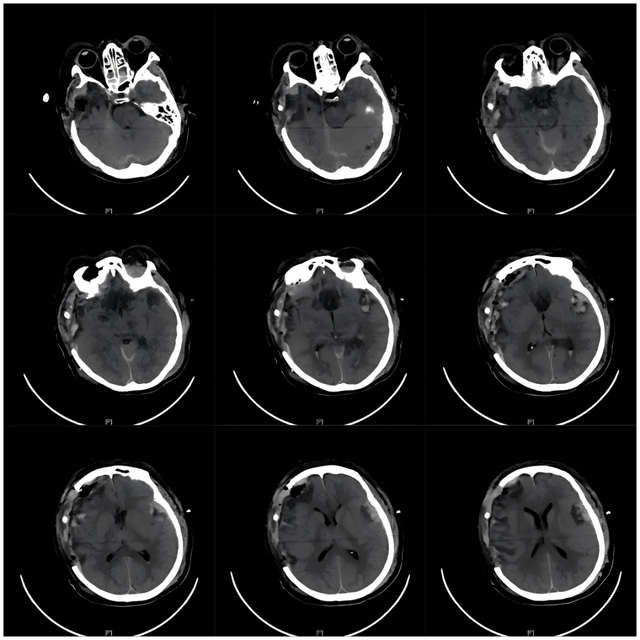

▲急诊术后CT影像

一年后随访显示,张女士的GCS评分已提升至11分(M6V1E4),根据CRS-R量表:患者已经脱离微小意识状态(eMCS)。

目前张女士已经能够自主进食、遵嘱完成动作,甚至呼唤家人的名字。“母亲端碗吃饭的那一刻,我忍不住哭了……感谢昆山市中医医院神经外科,是你们让我母亲获得新生!”儿子感慨道。